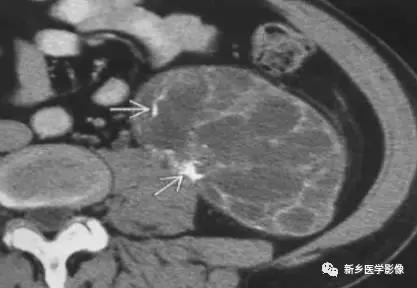

10、脾和肝肉芽肿

主要表现为点状的钙化,CT显示清晰,腹部平片有时候表现不明显。